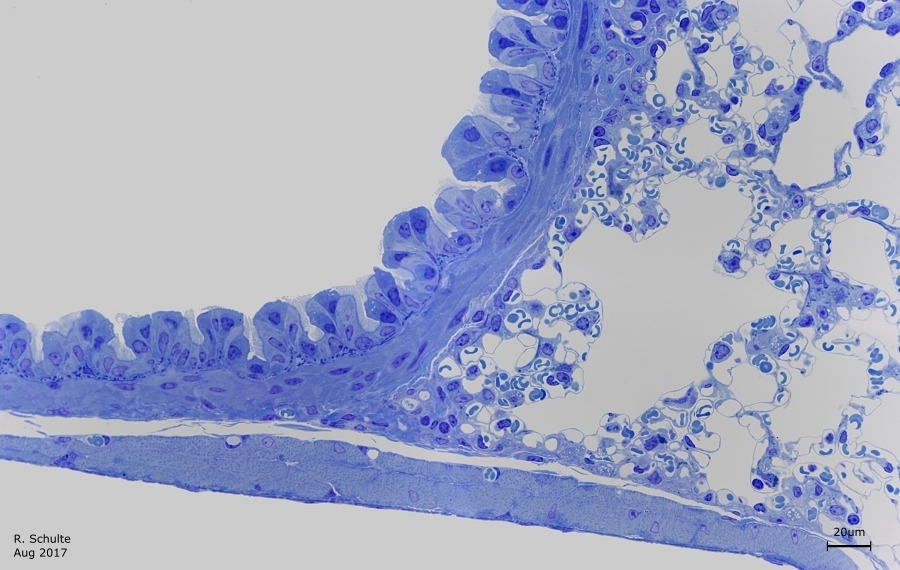

Die Schnittdicke liegt bei 0,8µm und die Farbung ist eine Basische Toluidin Farbung.

Zu sehen ist ein grosse Bronchiolus respiratorius mit oben davon ein begleitende A. pulmonalis.

Die zwei Rechtecken Markieren beide folgende Bilder.

Links das Einschichtiges prismatischen Epithels mit Flimmer-(Wimper-) Zellen und Flimmerlose Clara-Zellen. Rechts ist das Lungengewebe mit Alveolen zu sehen.